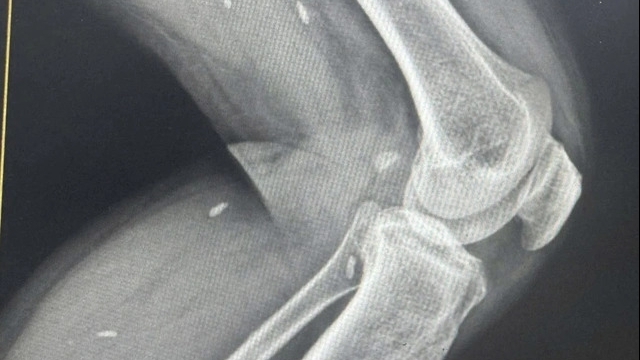

Bệnh nhân L.T.N.L (46 tuổi, trú tại xã Gio Linh, tỉnh Quảng Trị) nhập viện trong tình trạng sưng đau dữ dội vùng cổ - bàn tay, hạn chế vận động các ngón tay. Kết quả thăm khám cho thấy bệnh nhân bị viêm hoại tử nặng sau tiêm kháng viêm, chẩn đoán biến chứng sau điều trị hội chứng ống cổ tay.

Sau thời gian điều trị nội khoa không hiệu quả, các bác sĩ Khoa Ngoại Thần kinh đã chỉ định phẫu thuật cắt lọc mô hoại tử, giải phóng chèn ép thần kinh giữa bàn tay trái. Sau mổ, tình trạng bệnh nhân cải thiện rõ rệt, chuẩn bị tiếp tục phẫu thuật bàn tay phải.

Qua trường hợp này, các bác sĩ cảnh báo tiêm sai kỹ thuật có thể gây tàn phế vĩnh viễn. Theo đó, tiêm kháng viêm corticosteroid chỉ được chỉ định trong trường hợp hội chứng ống cổ tay mức độ nhẹ - trung bình, khi điều trị nội khoa không hiệu quả và phải được thực hiện tại cơ sở y tế có chuyên khoa.

Tiêm sai vị trí hoặc không đảm bảo vô khuẩn có thể gây tổn thương thần kinh giữa, viêm hoại tử gân, teo mỡ dưới da, lõm da vĩnh viễn hoặc nhiễm trùng nặng.